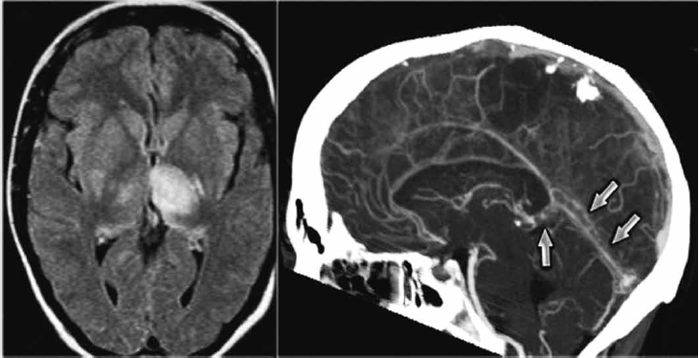

Observe a tomografia de crânio a seguir.

Feminina, 32 anos, chega ao pronto-socorro relatando cefaleia intensa e persistente de início súbito há 3 dias, associada a episódios intermitentes de diplopia. Refere que a dor é difusa, não pulsátil e tem piorado progressivamente. Faz uso de anticoncepcional oral combinado nos últimos dois anos, viagem recente longa (voo transatlântico), uma semana antes do início dos sintomas, e sem histórico prévio significativo para enxaqueca ou outras doenças neurológicas. Exame Físico: Pressão arterial: 130/85 mmHg; Frequência cardíaca: 78 bpm; Temperatura corporal: 36.8 °C e exame neurológico, inicialmente, sem alterações focais evidentes, além da diplopia ocasional durante períodos prolongados de fixação visual. Não há sinais meníngeos presentes nem déficits motores ou sensitivos localizados. Coletado líquor que se encontra dentro dos parâmetros normais. Considerando as informações e a tomagrafia apresentadas, qual a abordagem terapêutica inicial mais adequada para essa paciente?